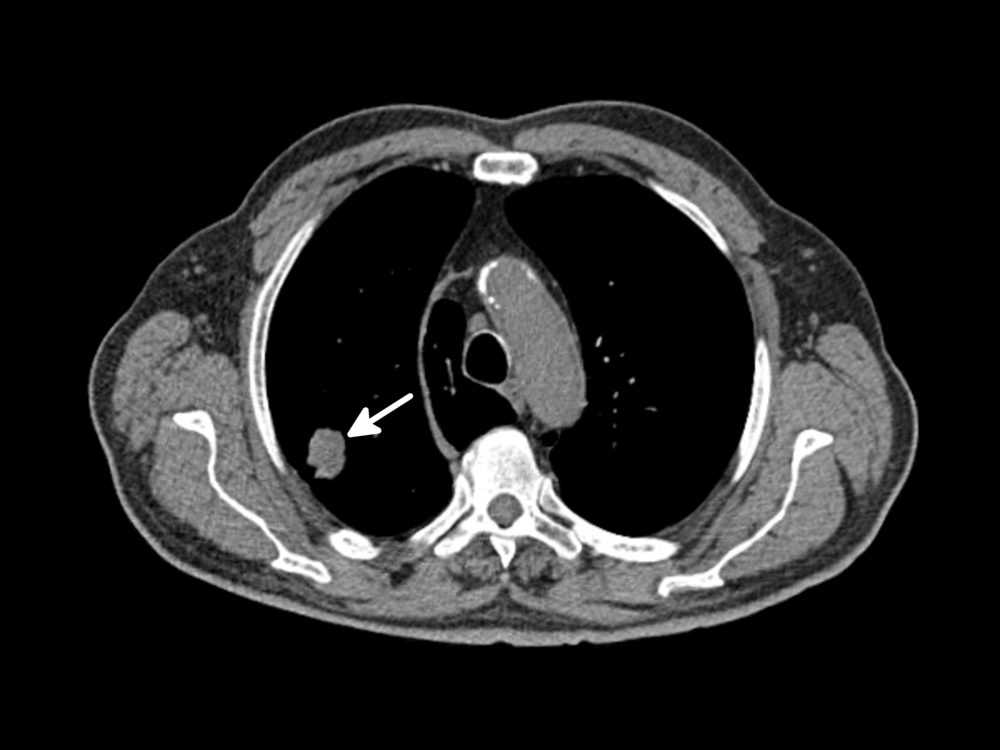

50 лет кт